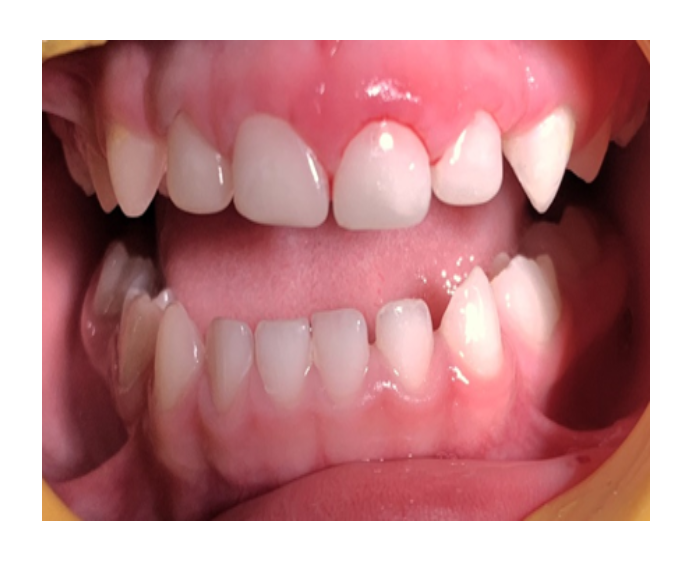

Mordida Cruzada anterior unidental